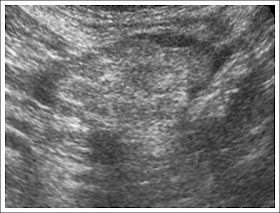

Las características ecográficas son:

Masa ovalada hiperecoica bajo el punto de máximo dolor

Halo hipoecoico en la periferia de la lesión

Adherida a la pared anterior peritoneal

No Compresible

En general de tamaño < 5 cm